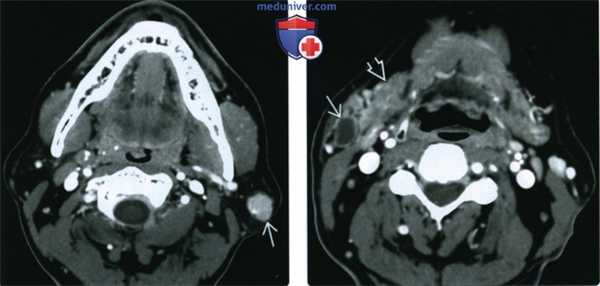

(Слева) КТ с КУ, аксиальная проекция. В поверхностной доле околоушной железы имеется круглое образование, равномерно накапливающее контрастное вещество. Мелкие опухоли Вартина могут накапливать контраст равномерно, но крупные новообразования обычно характеризуются неоднородным накоплением контрастного вещества.

(Справа) КТ с КУ, аксиальная проекция. Латеральнее поднижнечелюстной железы, в области хвоста околоушной железы, имеется кистозное образование. В большинстве случаев опухоль Вартина возникает в пределах самой железы, однако некоторые новообразования прорастают из окружающих лимфатических узлов.г) Патология:

(Слева) На аксиальной КТ с КУ в поверхностной доле околоушной железы визуализируется округлая опухоль, равномерно накапливающая контраст. Маленькие опухоли Уортина могут контрастироваться равномерно, в то время как для больших в целом характерно неравномерное накопление контраста.

(Справа) На аксиальной КТ с КУ возле хвоста околоушной железы визуализируется кистозное образование снаружи от поднижнечелюстной железы. Хотя большинство опухолей Уортина возникают в околоушной железе, некоторые могут обнаруживаться и в перипаротидных лимфоузлах.1. Общая характеристика: